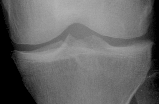

With these requirements in mind we experimentally come up with a layout comprised of six rectangular ROIs, two placed in femoral condyles and four in the head of tibia (cf. Figure 1).

Refer to captionF0subscript𝐹0\displaystyle F_{0}F1subscript𝐹1\displaystyle F_{1}T0subscript𝑇0\displaystyle T_{0}T1subscript𝑇1\displaystyle T_{1}T2subscript𝑇2\displaystyle T_{2}T3subscript𝑇3\displaystyle T_{3}med.lat.

Figure 1: Anchoring ROIs.

For consistency across the population we anchor the ROIs at anatomically meaningful landmarks and scale them proporionally.